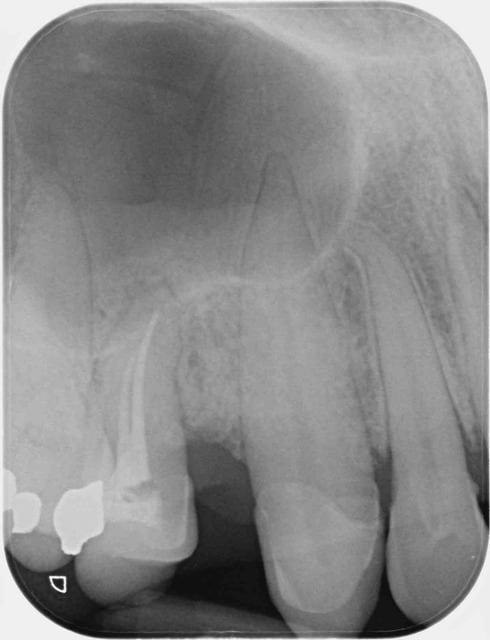

Je fais 95% de mes endos avec une anesthésie ostéocentrale. Les 5% restant sont des dents de sagesse maxillaires pour des patients chez qui le site entre 6 et 7 ne se prête pas à l'injection.

Et pis quelques échecs quand même dont cette 13 en pulpite +/- chronique, cet après-midi. La parapicale n'a pas eu plus d'efficacité. La faute au sinus + acidose.

Pour ta canine, j'aurai fait une osteo en mesial de 12 avec du 1/100.000, etant donné la proximité des sinus, et la proximité des racines de 12 et 13. En mésial de 12, tu peux aller profondément.